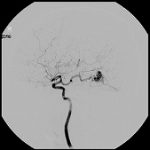

脳血管撮影

手術前

手術後